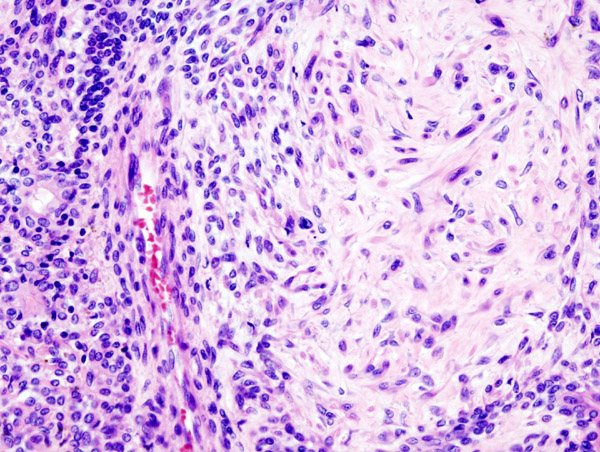

Warthin Tumor

Warthin tumor is a benign cystic tumor with a stroma that resembles a lymph node and many lymphocytes.

Warthin tumor is also known as papillary cystadenoma lymphomatosum.

Warthin tumor is the second most common salivary gland tumor.

Warthin tumor occurs almost invariably in the parotid.